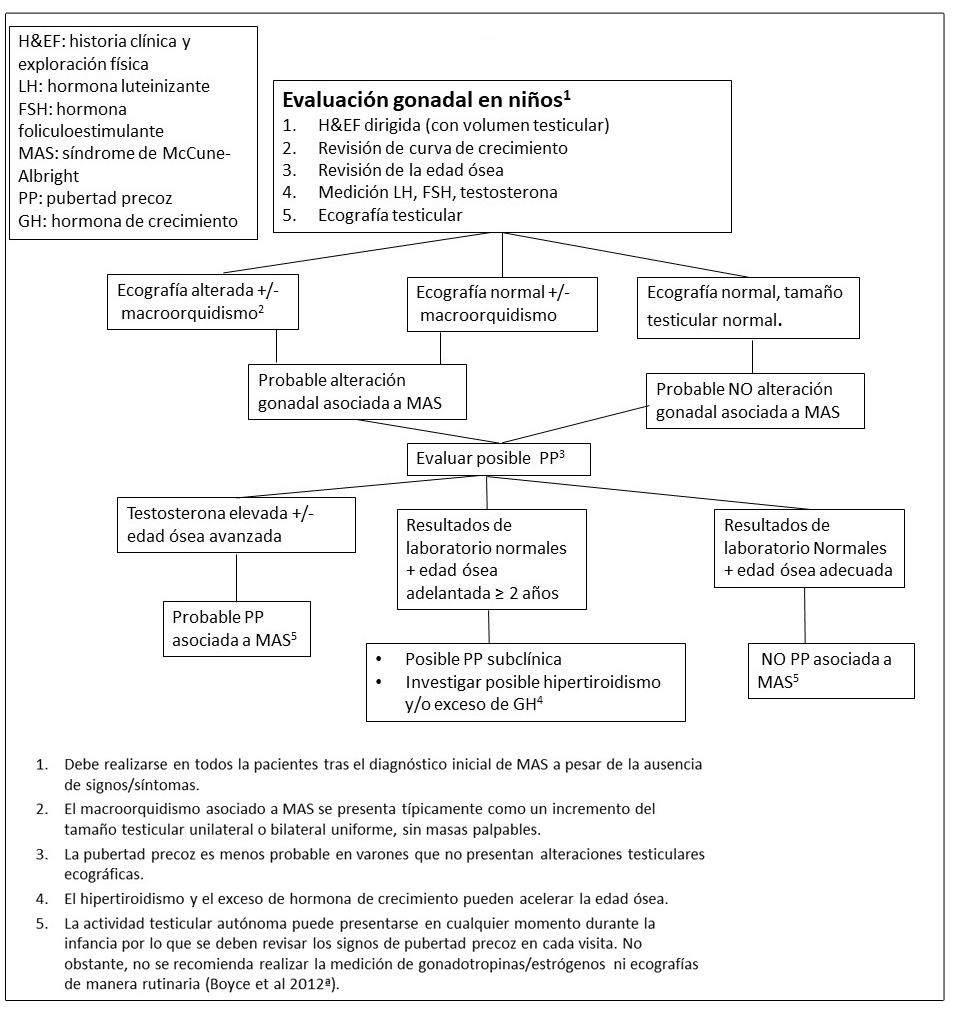

Figura 7. Pruebas y seguimiento recomendado para la evaluación gonadal de niños con Displasia Fibrosa/Síndrome de McCune-Albright

La pubertad precoz es menos frecuente en niños con DF/MAS (~10-15%), y es secundaria a la producción autónoma de testosterona (Boyce et al 2012a) resultando en un desarrollo puberal progresivo, incluyendo una aceleración en el crecimiento lineal, crecimiento de vello púbico y axilar, la aparición de acné, y el desarrollo de una comportamiento inapropiadamente agresivo y sexual.

Tanto en niños como en niñas con pubertad precoz, la producción autónoma prolongada de esteroides sexuales generalmente culmina en la activación del eje hipotálamo-hipofisario y en el desarrollo de pubertad precoz central.

Alteraciones testiculares.

Las alteraciones testiculares están presentes en la mayoría de varones con MAS (~85%), y típicamente se manifiestan como macroorquidismo unilateral o bilateral (Boyce et al 2012a). La exploración ecográfica suele mostrar discretas lesiones hiper e hipoecoicas así como microlitiasis, las cuales corresponden a áreas de hiperplasia de células de Leydig y/o Sertoli (Ver Figura 4B).

Se desconoce el potencial de malignización de estas lesiones testiculares, pero los estudios clínicos disponibles indican que es muy bajo (Boyce et al 2012a).